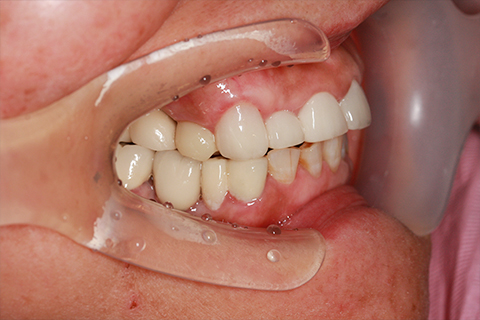

症例3

治療前

インプラント埋入時

治療後

- 年齢・性別

- 60歳男性

- 治療期間

- 2ヶ月

- 抜歯

- なし

- 治療費

- 61.6万円

- 備考

- 右下6.7欠損

- 治療内容

- 右下6.7欠損部にインプラント埋入

- 施術の副作用(リスク)

- オペによる知覚障害。インプラントによる歯肉炎。インプラント脱落。